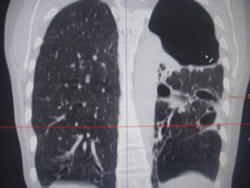

Больная с 03 года выявлена с диагнозом ФКТЛ. Ведет асоциальный о  браз жизни, лечится по настроению. На снимках- одни страсти и таких живучих больных- хроников уже мало. Абацилирована с 06года, если бы высевала, ведя такой образ жизни, давно бы сгинула.

Впечатляет...

Ну, что ж, ей крупно повезло, что есть запаска в виде еще одного легкого.

Ну да, правое тоже поражено, но не в таком виде.

Да, по всей видимости, на обычных рентгенограммах, возможно и томограммах, картинка весьма напоминает фиброзно-кавернозный туберкулёз, который, как трактует фтизиатрия относится к запущенным формам туберкулёза, за который ох как сильно бьют!

Не могу сказать, что видел сильно много ФКТ, но видел..., а представленный случай, на мой взгляд ФКТ не "пахнет". При таких то полостищах, а может быть и кистах слева, довольно интеллигентная картинка справа...

А может быть то не бывшие "каверкоты", а дизонтогенетические кисты?